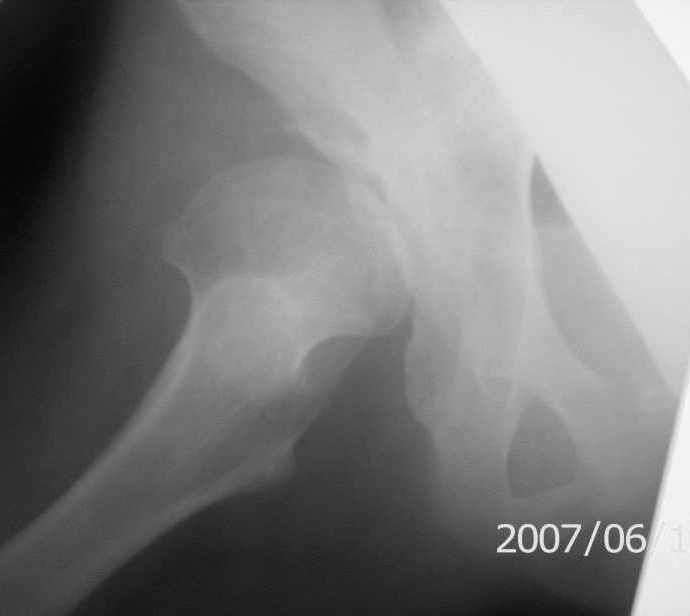

Re: Дисплазия тазобедренного сустава 14 лет

снимки